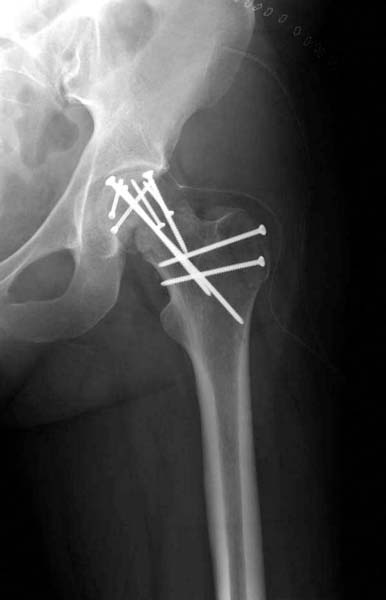

Трудно выбрать приоритет, когда имеется одинаковые по значимости, по сложности повреждения и с вовлечением различной локализации. У пожилых переломо-вывих головки бедра можно было бы проигнорировать, но у молодых такое решение привело бы к катастрофе, и поэтому приоритет первичной фиксации отдали решению переломо-вывиха таранной кости и головки бедра.

Больная стабильная после хирургических мероприятии и получив добро, приступили к закрытому вправлению таранной кости с укладкой наружного фиксатора. Затем укладка больную на бок и открытый остеосинтез перелома-вывиха головки бедра.

По характеру повреждения головка находится сзади и напрашивается задний Кохер-Лангенбек доступ, но в заднем доступе имеется риск повреждения магистрального кровоснабжения головки a. circumflexa. Более щадящая trochanteric flip (digastric osteotomy) сохранит кровоснабжение и дасть возможность работу при вывихнутом суставе.

Остеосинтез бедра не стали делать из-за множественных переломов ребер с ушибом грудной клетки и поэтом у закончили фиксацию бедра наружным фиксатором.